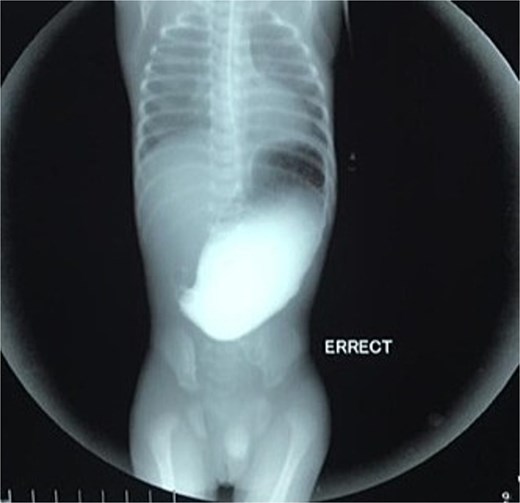

Initial management included nil per oral, fluid resuscitation, and nasogastric tube insertion. Laboratory investigations were unremarkable. Plain abdominal radiography revealed a single gastric air bubble with no distal gas, consistent with gastric outlet obstruction (Fig. 1). An upper gastrointestinal contrast study confirmed pyloric obstruction, with no contrast passing into the duodenum (Fig. 2).

Upper gastrointestinal contrast study demonstrating pyloric obstruction.

The diagnosis of PA is typically confirmed postnatally based on clinical presentation, radiographic findings, and intraoperative exploration. Non-bilious vomiting, abdominal distension, and failure to pass stool are common clinical features, as seen in our patient [8]. Plain abdominal radiography often reveals a single gastric air bubble with no distal gas, while contrast studies demonstrate failure of contrast to pass beyond the pylorus, as observed in our case [9]. These findings are consistent with gastric outlet obstruction, which is pathognomonic for PA.